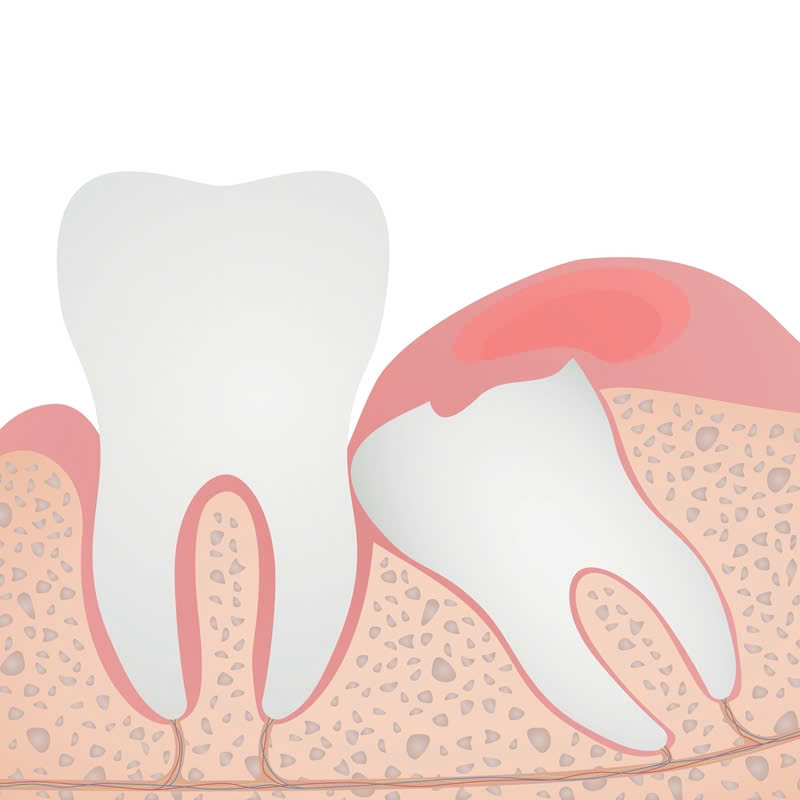

Nhổ răng bằng máy Piezotome là một kỹ thuật nhổ răng hiện đại, sử dụng sóng siêu âm để cắt nướu và xương hàm, giúp việc tách răng khỏi ổ răng dễ dàng hơn. Kỹ thuật này mang đến nhiều ưu điểm, đặc biệt là trong những trường hợp nhổ răng khó, như răng khôn mọc ngầm, răng sâu, răng bị chèn ép…

- Thích hợp cho những trường hợp nhổ răng khó: Phương pháp này đặc biệt phù hợp với những trường hợp nhổ răng phức tạp như răng khôn mọc ngầm, răng sâu, răng bị chèn ép…

- Những người cần nhổ răng khôn mọc ngầm, răng sâu, răng bị chèn ép…

- Răng khó nhổ: Một số trường hợp như răng bị gãy hoặc nằm lệch có thể làm cho việc nhổ răng phức tạp hơn, cần cân nhắc kỹ lưỡng.